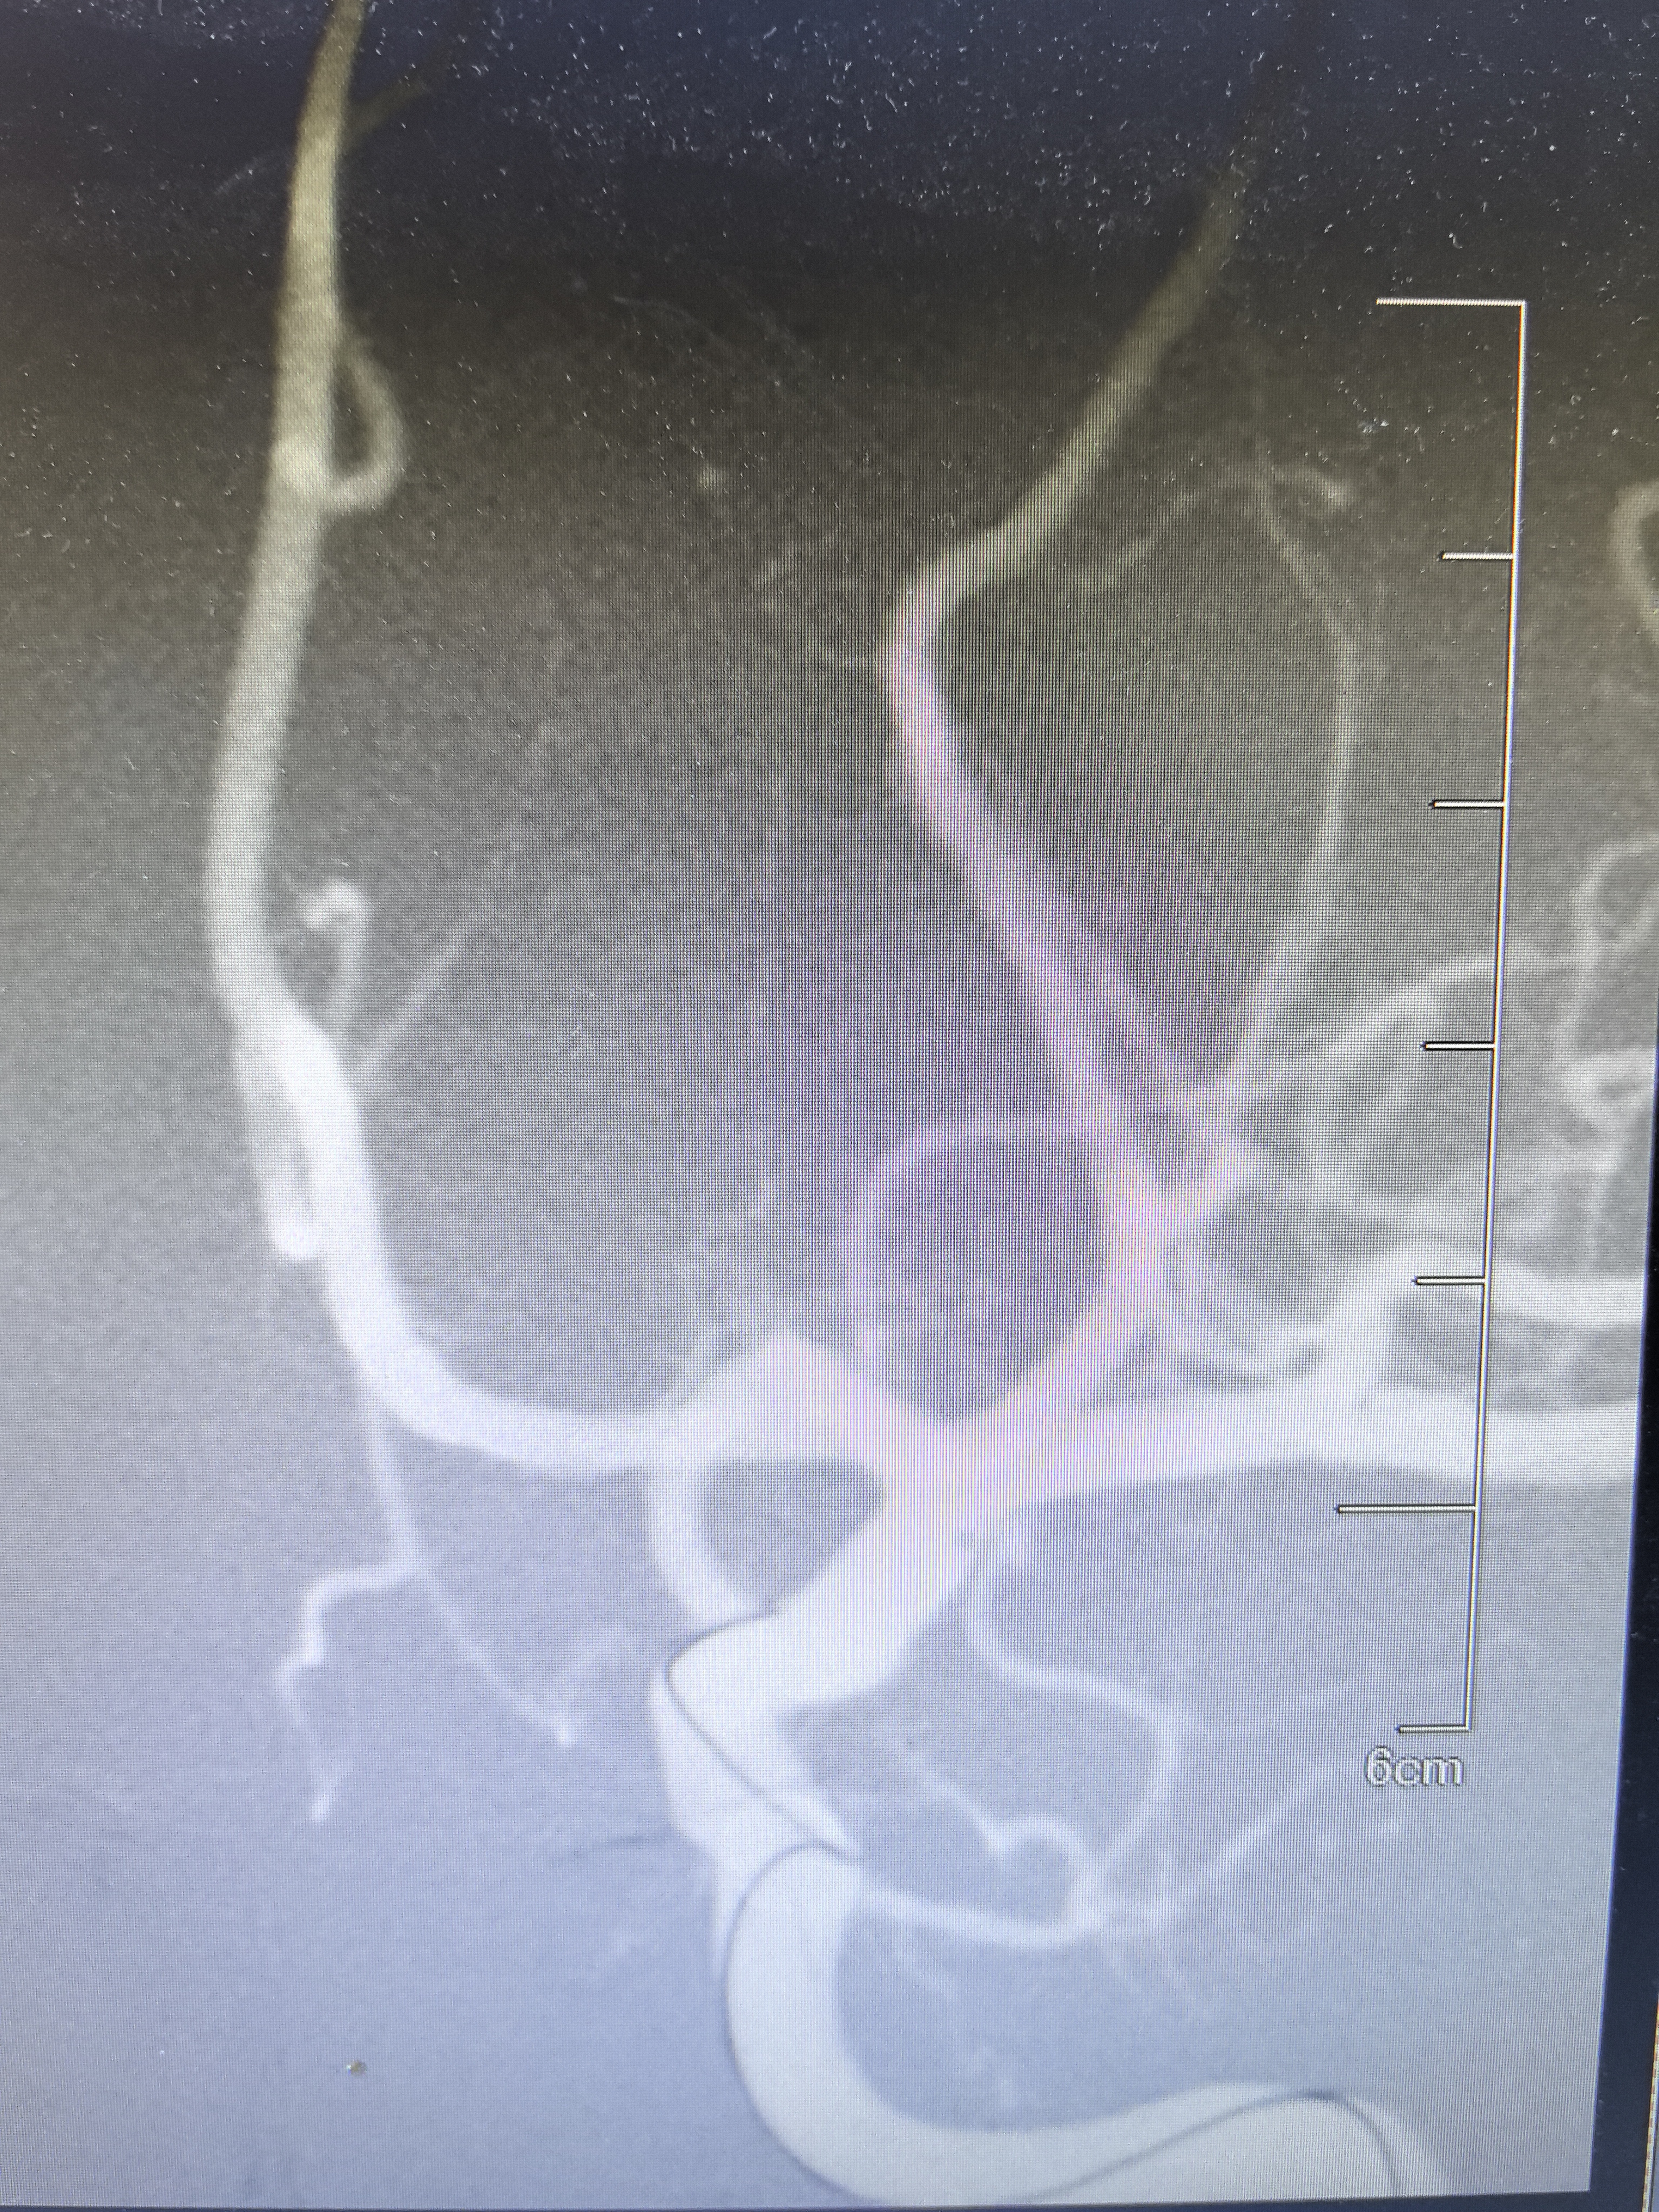

0.014微导丝可以进去瘤内,微导管进入瘤内困难

缓慢撤出微导丝,微导管位于瘤颈口尚稳定

完全撤出微导丝,微导管于瘤颈口稳定